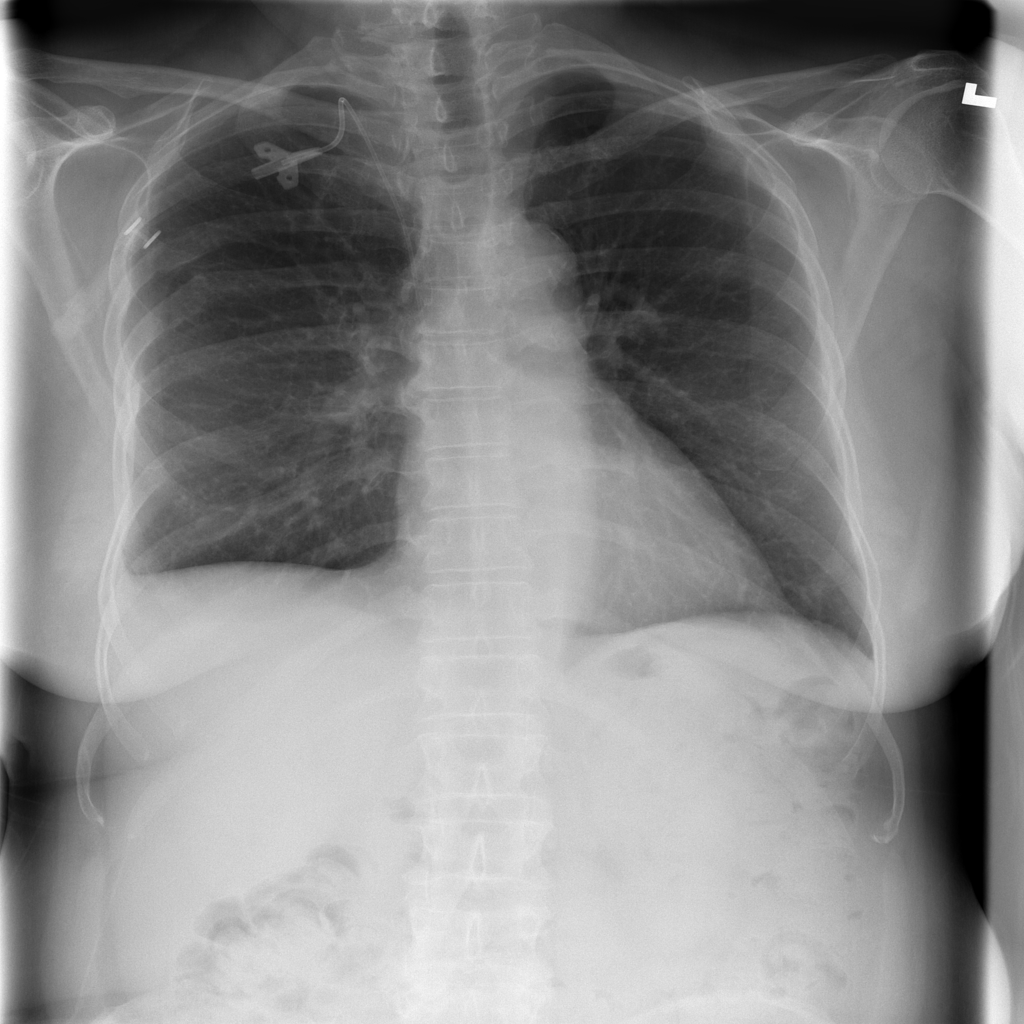

PAT-C77C · IMG-003Fibrosis

PAT-C77C · IMG-003

PA